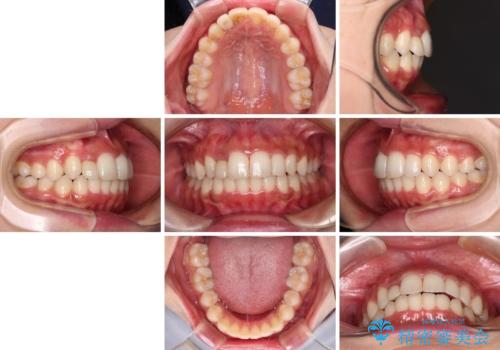

抜けてしまうと言われた前歯 インビザラインによる矯正治療

- 上下前歯のデコボコを気にして来院された患者様です。

前歯のセラミックが装着されている歯は、歯根が短くなっており、他院では抜けてしまうので矯正はできないと言われていたようです。

患者様と相談し、抜けてしまった場合にはインプラントあるいはブリッジによる補綴治療が必要となることを確認し、極力歯根に負担のかからないような仕上がりで治療を進めて行くこととしました。

デコボコを解消には、IPR(歯と歯の間を削る)をメインに歯列排列を設計し、インビザラインにて矯正治療を行うこととしました。

レントゲン写真上では、矯正治療前後で歯根長さに大きな違いはなく、抜歯を回避することができました。

上顎内側に転位している前から2番目の歯は移動が難しく、無理矢理歯根全体を動かそうと設計すると、歯肉退縮・歯髄壊死・歯根吸収といった危険性が増すため、無難なゴールにて治療を終えることとなりました。